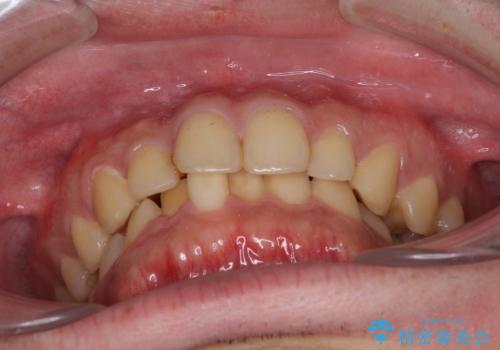

- 上下前歯のデコボコと下の前歯が隠れるほどの深い咬み合わせを気にして来院された患者様です。

インビザラインによる上下歯列の拡大と、IPR(歯と歯の間を削る)にるスペースの獲得により、口元のデコボコとディープバイトを改善することとしました。

デコボコがなくなったことで日頃の清掃が行いやすくなり、深い咬み合わせが改善したことで、食いしばりによる顎の負担も軽減されました。